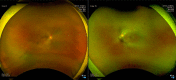

Retinitis pigmentosa can be associated with exudative vasculopathy in rare instances, which can manifest as retinal vasoproliferative tumours. We present the case of a 33-year-old woman previously diagnosed with retinitis pigmentosa sine pigmentosa in both eyes. She was asymptomatic and just came in for a routine follow-up eye examination. Thorough examination of the peripheral retina on the right eye revealed a dome-shaped retinal tumour with a feeder vessel and surrounding exudative changes at the superotemporal periphery, consistent with a secondary retinal vasoproliferative tumour from retinitis pigmentosa. She subsequently underwent focal laser photocoagulation of the tumour which resulted in tumour stabilisation. While exudative vasculopathy is very uncommon in retinitis pigmentosa, ophthalmologists need to be aware of its occurrence in such patients. Vision loss may occur from exudation, haemorrhage, retinal detachment and neovascularisation. A thorough examination of the peripheral retina is warranted in these cases.